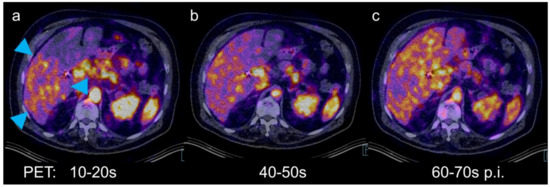

Dynamic PET/CT with the Hepatobiliary Tracer [68Ga]Ga-Tmos-DAZA for Characterization of a Hepatic Tumor

Freesmeyer, M.; Greiser, J.; Winkens, T.; Gühne, F.; Kühnel, C.; Rauchfuß, F.; Tautenhahn, H.-M.; Drescher, R. Dynamic PET/CT with the Hepatobiliary Tracer [68Ga]Ga-Tmos-DAZA for Characterization of a Hepatic Tumor. Diagnostics 2021, 11, 660. https://doi.org/10.3390/diagnostics11040660